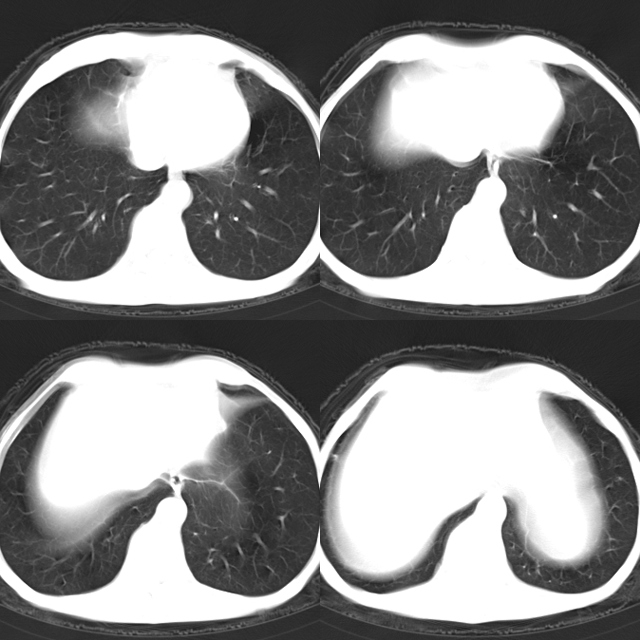

以下是引用心路寻觅在2010-4-17 18:35:00的发言:[br]纵膈多组淋巴结肿大呈“冰冻纵膈”,左肺上叶空洞伴其内结节密度影,考虑淋巴瘤伴左肺上叶曲霉菌感染。[br][br][本贴已被 心路寻觅 于 2010-4-17 18:36:23 修改过]

以下是引用zhangzhongshou在2010-4-17 19:32:00的发言:[br]一元论考虑左肺空洞型肺癌并纵隔淋巴结转移可能性大。